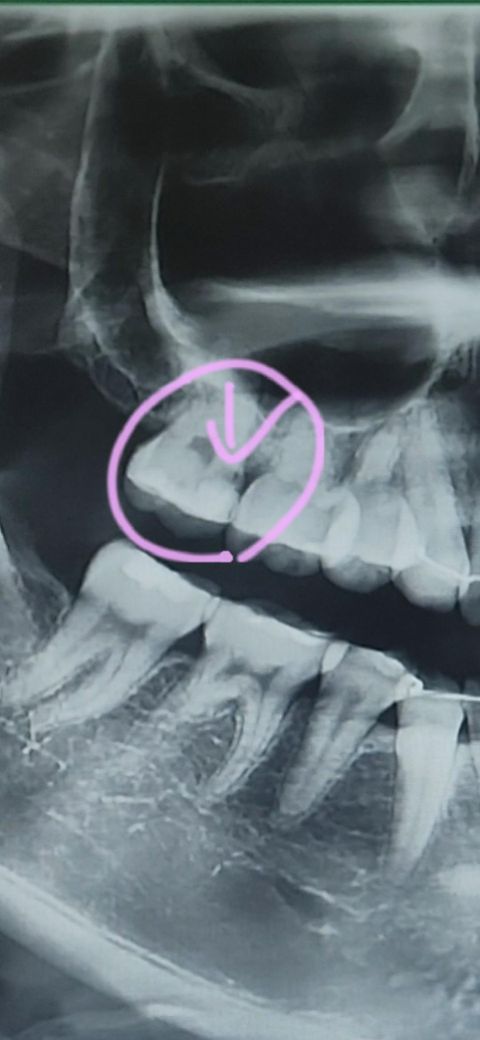

아래 사진은 오늘 간 B 치과이고 표시한 부분에 검은 점은 안 보입니다. 사이사이 충치는 있지만 크지 않아 정기검진을 통해 지켜보자고 하셨습니다.

맨 아래 사진은 6년전쯤 찍은 사진입니다.

• 3번 째 사진